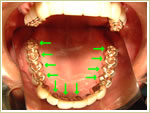

59歳 男性 インプラント埋入数:12本 |

| 治療前 |